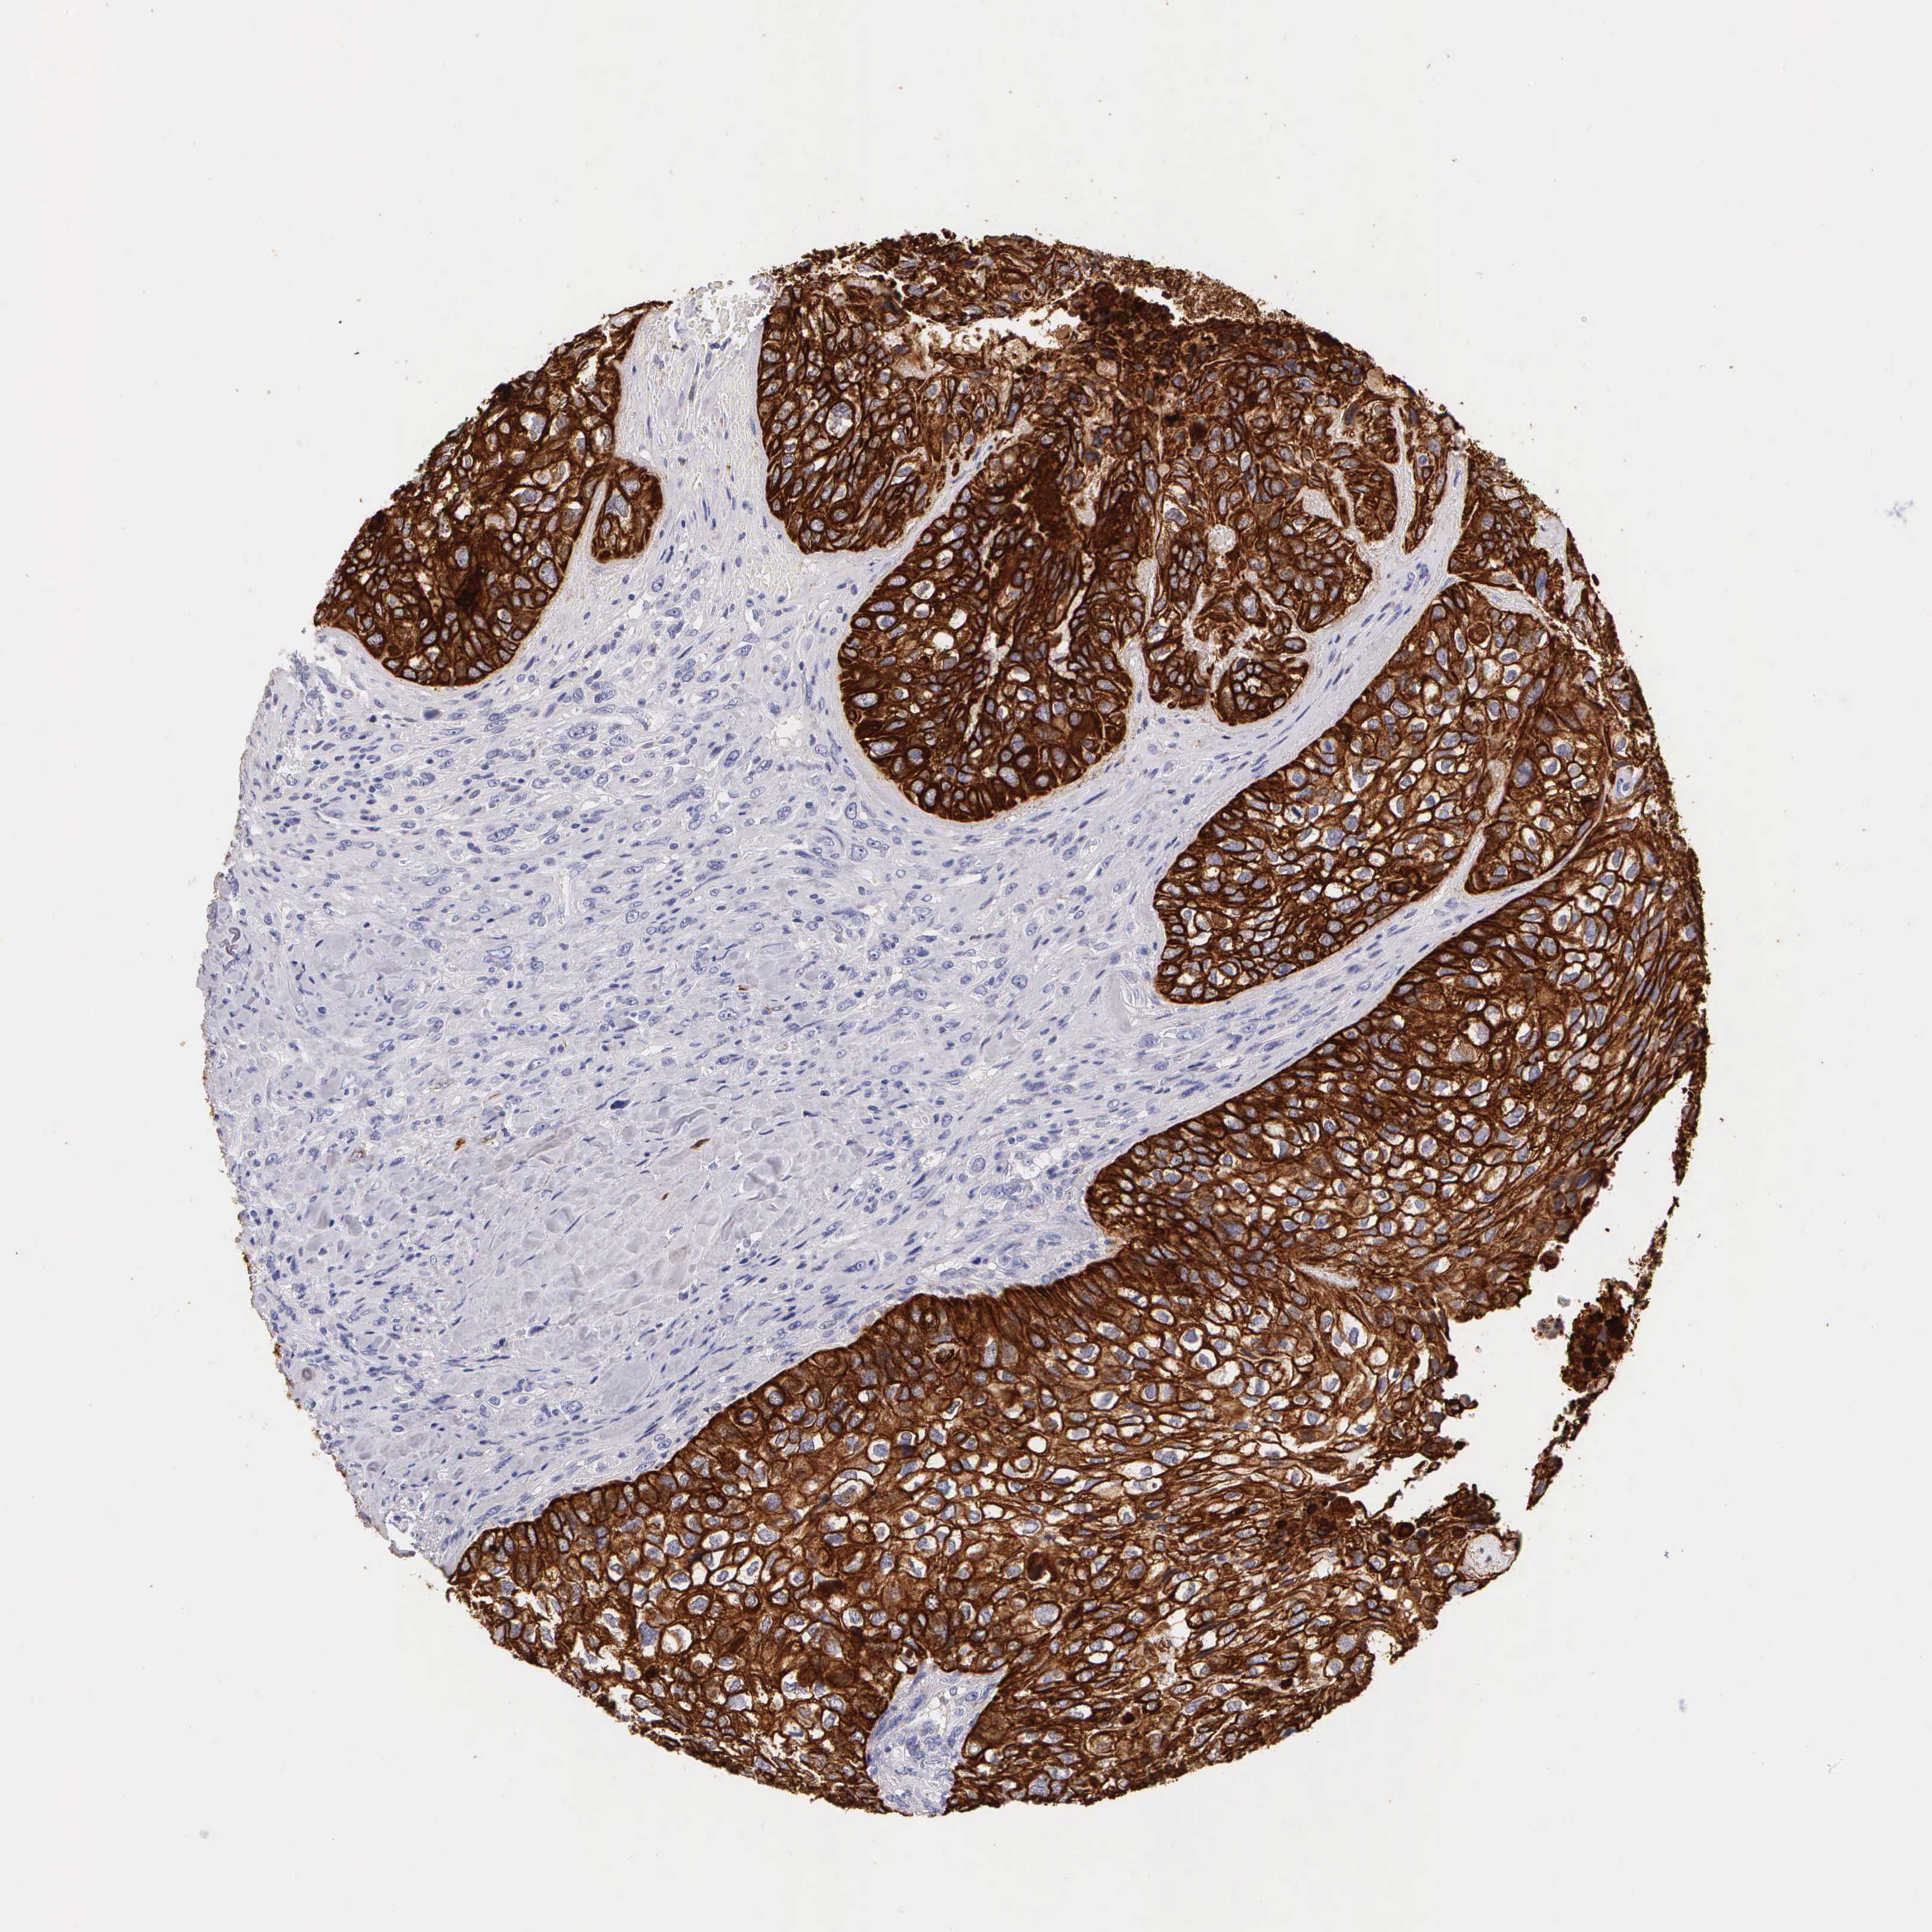

CANCER BREAST CANCER Show tissue menu

BRCA TCGA BRCA VALIDATION PROTEIN EXPRESSION

ANTIBODIES

AND

VALIDATION